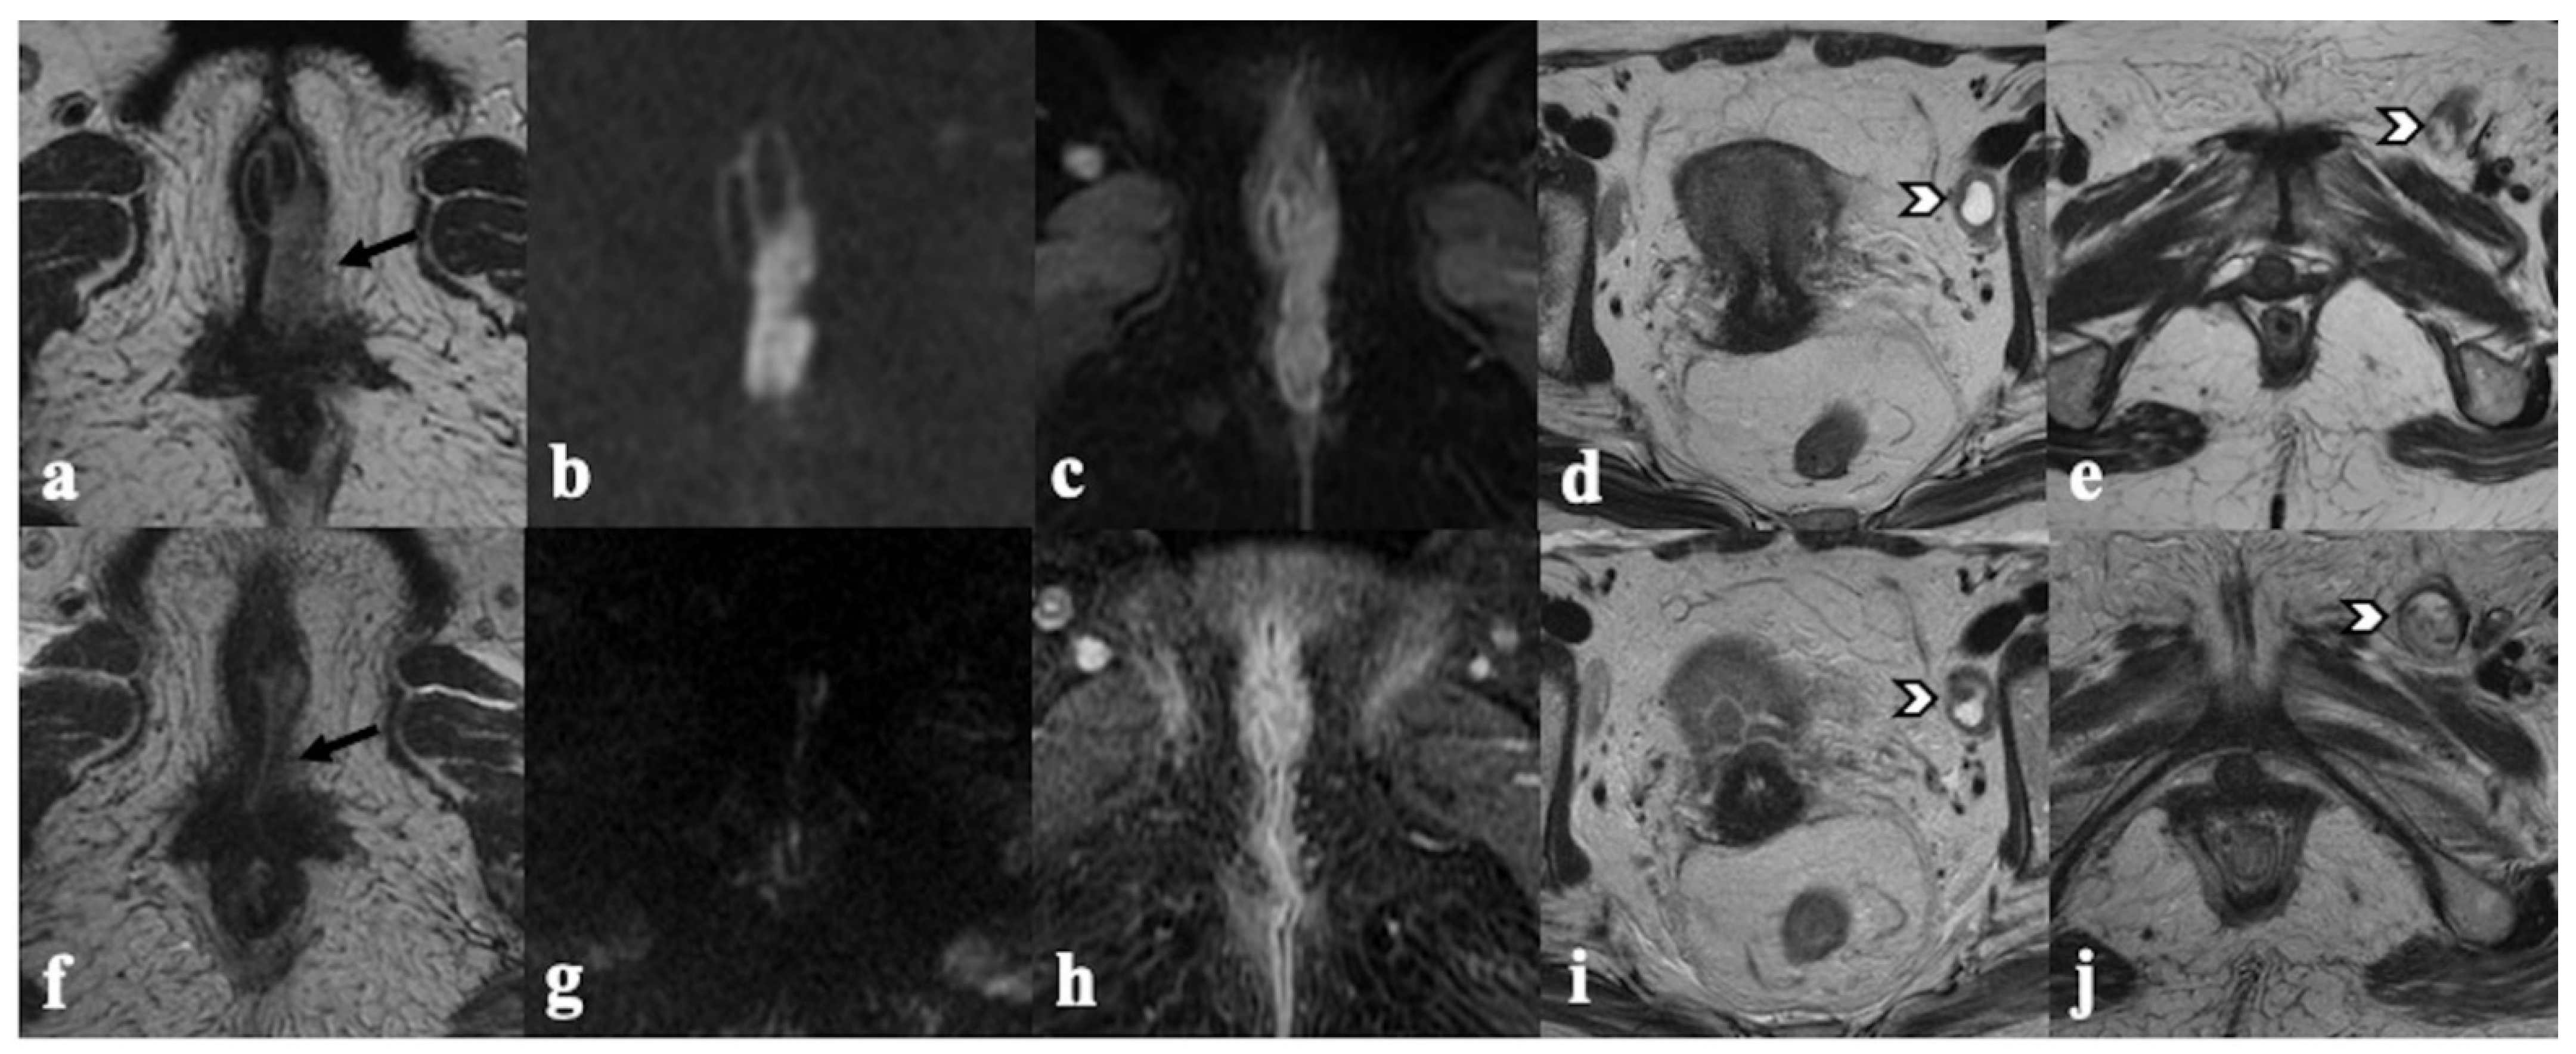

3.1. Vagina

3.2. Urethra

3.3. Anal Sphincter Complex

4. Post-CRT MRI Findings

4.1. Local Tumor Status and Residual Invasion of Adjacent Organs

4.2. Lymph Node Status